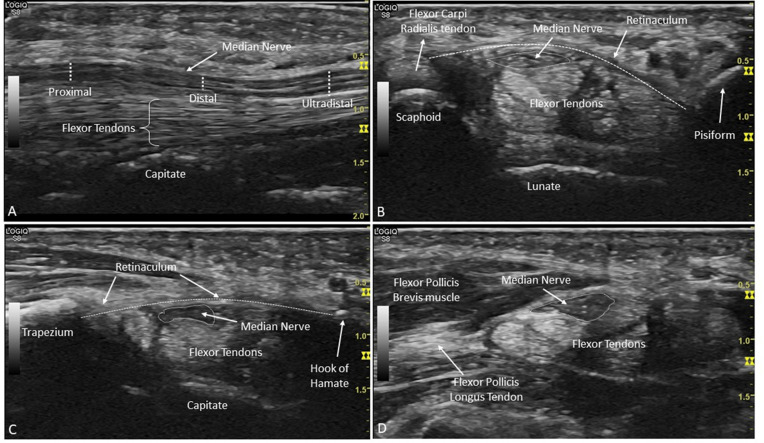

Methods: Patients clinically diagnosed with primary CTS and healthy controls were included. The MN-CSA was measured by US at three wrist levels: proximal, distal and ultradistal. The best cut-off to differentiate cases and controls was determined for the CSA and for the difference between levels of the same wrist. The performance of different definitions for US-CTS compared with the clinical diagnosis of CTS was evaluated: (1) CSA above cut-off at each level; (2) CSA-difference above cut-off at each level; (3) ≥1 level with CSA above cut-off and (4) ≥1 CSA-difference above cut-off. Definition 3, excluding the ultradistal level, and combinations of definitions were also tested.

Results: In total, 219 patients and 39 controls were included. The CSA was higher in patients (10.5-16.8 mm2) than controls (6.2-7.6 mm2). The difference between groups was maximal at the ultradistal level (right: 10.1 mm2; left: 8.3 mm2). The CSA cut-offs were 11 mm2, 9 mm2 and 10 mm2 at the right, and 10 mm2, 8 mm2 and 10 mm2 at the left, for the proximal, distal and ultradistal levels, respectively. Definition 3 yielded the best balance between sensitivity (98%) and specificity (95%) (right hand). Removing the ultradistal level from definition 3 decreased sensitivity to 90%, maintaining the same specificity.